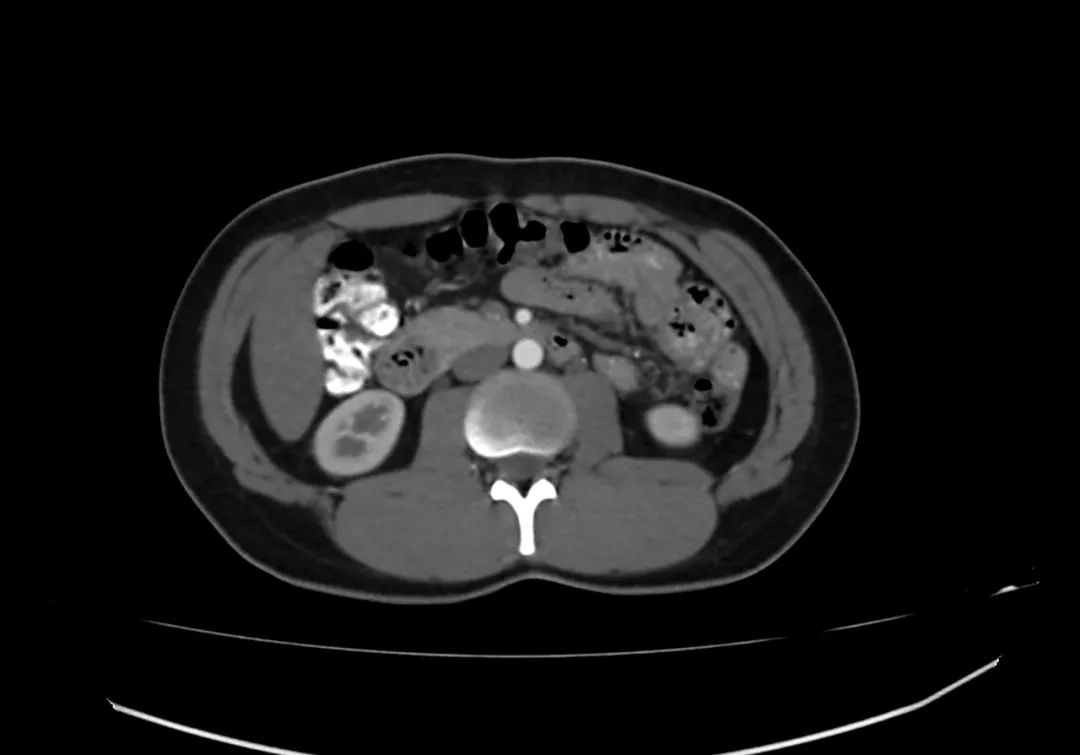

动脉期上腹部轴向增强图像显示胰腺完全包围十二指肠第二部,与完全性环状胰腺一致。